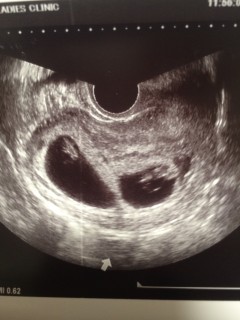

前回6w3dの時は、どっちも胎芽4.5㎜で小さめかな?と不安でしたが、今回7w3dで12.5㎜★2人とも同じサイズで成長してくれてるのが嬉しいです(T^T)心拍確認も2回目で、ようやく安心できそうです。